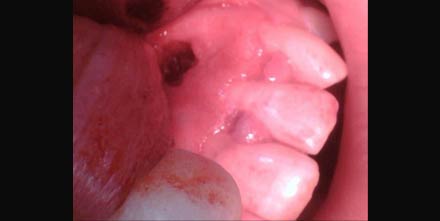

tooth During the procedure, your dentist or endodontist cuts through your gum and pushes the gum tissue aside in order to reach the root. Usually just a few millimeters of the root are removed, as is any infected tissue surrounding the root.

tooth The tissue will then be sutured (stitched), so your gum can heal and grow back in place. Your jawbone will also eventually heal around the filling at the end of the root. You shouldn’t feel much, if any, pain or discomfort during the procedure.